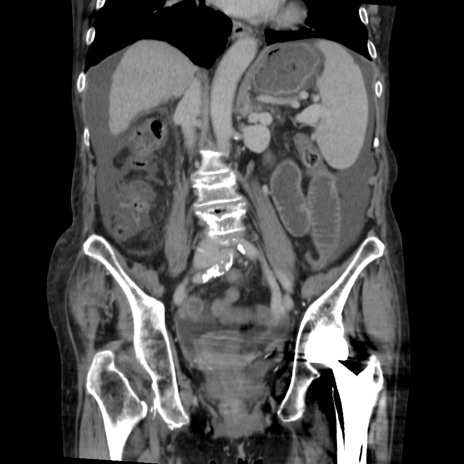

症例31(冠状断像)

【症例】80歳代 女性

【主訴】腹部膨満感

【現病歴】他院にて肝硬変にてフォロー中。1週間前から便秘、腹部膨満感、臍部腫瘤あり受診となる。

【既往歴】肝硬変

【身体所見】腹部膨隆あり、皮膚変化なし、疼痛なし。

【データ】WBC 4600、CRP 0.25